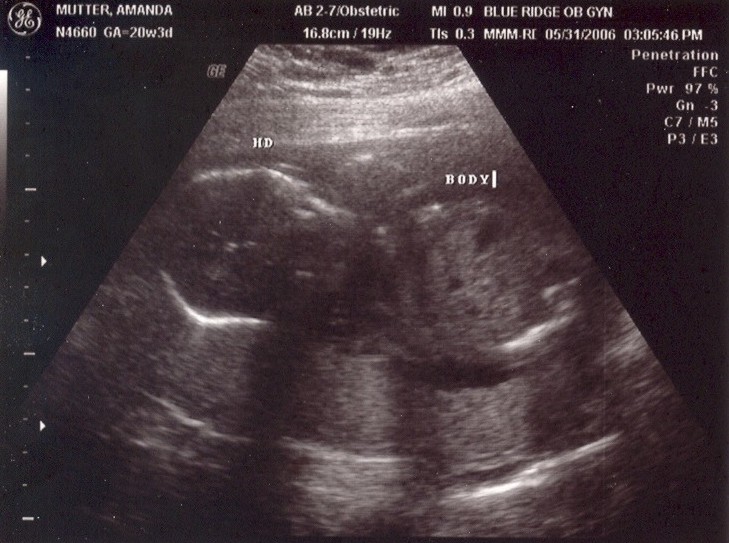

May 31, 2006: Diagnostic Ultrasound

OBs regularly do these to check if babies have all the right number of arms, brains, etc.